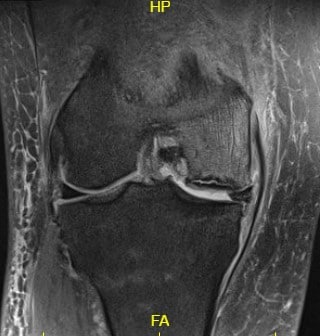

Imaging studies revealed severe osteoarthritis of the medial compartment of the right knee along with patellofemoral arthritis. MRI revealed progression of previous subchondral fracture at the medial femoral condyle now resulting in a region of avascular necrosis and prominent fluid-filled subchondral fracture line measuring up to 2.8 cm. There was a mild collapse of the articular margin and severe surrounding bone marrow edema.

There was a progression of the medial meniscal tear now with a high-grade tear at the posterior root attachment. Considering lifestyle limiting knee pain with avascular necrosis and arthritis of the right knee. The patient was advised right total knee replacement with custom instruments. She agreed with the plan.

T2 weighted image showing the coronal section of the knee with altered bone marrow signal and rim sign.